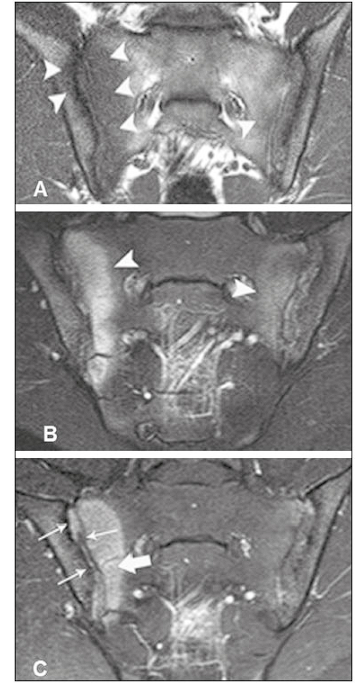

Achados inflamatórios na RM na Spa? (4)

1. Edema ósseo (osteíte) subcondral;

2. Capsulite;

3. Sinovite;

4. Entesite.

RM+ para sacroiliíte ?

1. Edema subcondral em uma área em mais de 1 corte ou;

2. Edema subcondral em mais de uma área no mesmo corte.

Procurar nas sequências STIR, T2 FATSAT,

T1 pós-Gd (para sinovite, porém não entra como critério)